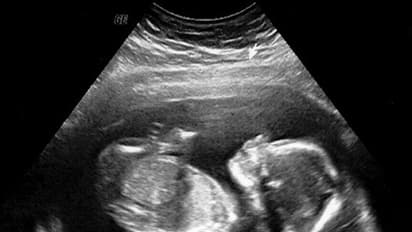

ವಾರಣಾಸಿ(ಸೆ.16): ಜಾರ್ಖಂಡ್'ನ ವಾರಣಾಸಿಯಲ್ಲಿ ವೈದ್ಯಕೀಯ ಲೋಕವನ್ನೇ ಚಕಿತಗೊಳಿಸಿದ ಅಚ್ಚರಿಯೊಂದು ನಡೆದಿದ್ದು, 6 ವರ್ಷದ ಪುಟ್ಟ ಕಂದಮ್ಮನ ಹೊಟ್ಟೆಯಲ್ಲಿ ಸತ್ತ ಭ್ರೂಣವೊಂದು ಪತ್ತೆಯಾಗಿದೆ. ಆ ಪುಟ್ಟ ಕಂದನ ಹೊಟ್ಟೆಯಲ್ಲಿ ಭ್ರೂಣ ಬಂದಿದ್ದು ಹೇಗೆ ಇಲ್ಲಿದೆ ವಿವರ.

ತೀವ್ರ ಹೊಟ್ಟೆ ನೋವಿನಿಂದ ಬಳಲುತ್ತಿದ್ದ ವಾರಣಾಸಿ ಗಡ್'ವಾ ಜಿಲ್ಲೆಯ 6 ವರ್ಷದ ಬಾಲಕನನ್ನು ಇಲ್ಲಿನ ಖಾಸಗಿ ಆಸ್ಪತ್ರೆಯೊಂದಕ್ಕೆ ಚಿಕಿತ್ಸೆಗಾಗಿ ದಾಖಲಿಸಲಾಗಿತ್ತು. ತಪಾಸಣೆ ನಡೆಸಿದ ವೈದ್ಯರು ಹೊಟ್ಟೆಯಲ್ಲಿ ಗಂಟಿನಂತ ಬೆಳವಣಿಗೆಯಾಗಿದೆ ಎಂದು ಆತನ ಮನೆಯವರಿಗೆ ಆಪರೇಷನ್ ಮಾಡಬೇಕೆಂದಿದ್ದರು. ಆದರೆ ಆಪರೇಷನ್ ವೇಳೆ ವೈದ್ಯರೇ ಬೆಚ್ಚಿ ಬಿದ್ದಿದ್ದು, ಬಾಲಕನ ಹೊಟ್ಟೆಯಲ್ಲಿ ಸತ್ತ ಭ್ರೂಣ ಪತ್ತೆಯಾಗಿದೆ. ಆದರೆ ಇಂತಹ ಪ್ರಕರಣ ಈ ಮೊದಲೂ ಬೆಳಕಿಗೆ ಬಂದಿವೆ ಎಂದು ತಿಳಿಸಿದ ವೈದ್ಯರು ಪ್ರತಿ 5 ಲಕ್ಷದಲ್ಲಿ ಒಂದು ಮಗುವಿಗೆ ಹೀಗಾಗುತ್ತದೆ.

ಇದೊಂದು ಅಪರೂಪದ ಸಂಗತಿ ಎಂದು ವೈದ್ಯರು ತಿಳಿಸಿದ್ದರೂ ಮಗುವಿನ ಹೊಟ್ಟೆಯಲ್ಲಿ ಭ್ರೂಣವಿರಲು ಹೇಗೆ ಸಾಧ್ಯ? ಎಂಬ ಪ್ರಶ್ನೆ ಕಾಡುತ್ತದೆ. ಈ ಪ್ರಶ್ನೆಗೆ ಉತ್ತರ ನೀಡಿರುವ ವೈದ್ಯರು ಇಂತಹ ಮಕ್ಕಳು ತಾಯಿಯ ಹೊಟ್ಟೆಯಲ್ಲಿ ಅವಳಿ ಜವಳಿ ಇರುತ್ತವೆ. ಆದರೆ ಕೆಲ ಕಾರಣಗಳಿಂದ ಒಂದು ಮಗುವಿನ ಬೆಳವಣಿಗೆ ಆಗುವುದಿಲ್ಲ. ಹೀಗಾಗಿ ಸಶಕ್ತವಾಗಿರುವ ಭ್ರೂಣ ವಿಕಾಸಗೊಳ್ಳದಿರುವ ಭ್ರೂಣದ ಮೇಲೆ ಹಿಡಿ ಸಾಧಿಸಿಕೊಳ್ಳುತ್ತದೆ ಹಾಗೂ ಅದರ ಹೊಟ್ಟೆಯಲ್ಲೇ ಬೆಳೆದುಕೊಳ್ಳುತ್ತದೆ. ರಿತೇಶ್'ನೊಂದಿಗೆ ಹೀಗೇ ಆಗಿದೆ ಎಂದಿದ್ದಾರೆ.